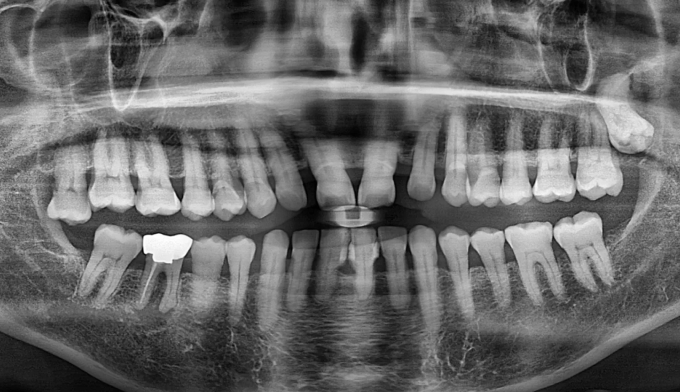

기존에 아래 앞니 사이 공간들에 레진이라는 치아색 나는 재료로 메워놓으셨던 분입니다. 나이가 들면서 잇몸이 약해지게되고 앞니가 점점 더 벌어질 수 있습니다.

타치과에서 다시 레진으로 공간을 없애려고 하였으나 더이상의 보철치료를 원하지 않으셔서, 기존에 존재하던 레진을 제거하면서 동시에 앞니 사이 공간을 교정치료를 이용해 닫아주기로 하였습니다.

기존에 앞니가 벌어지게 된 이유인 치주염을 치료하면서 동시에 앞니 공간을 교정을 통해 닫아줍니다.

총 교정기간은 9개월입니다.